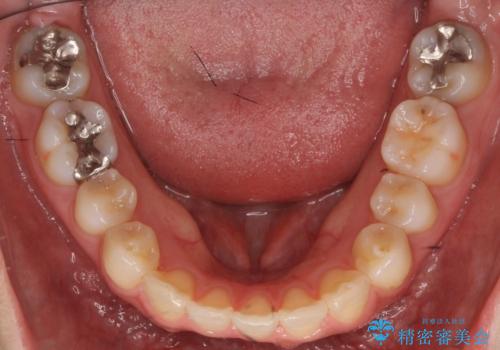

下の前歯が生まれつき3本でした。

下を3本でそのまま並べてあるため、上下の正中は合いません。

合わせようとすると抜歯か、下の隙間を無理やり開けてブリッジとなりますが、そこまでするメリットがないため、下はそのままの歯の数を生かしています。